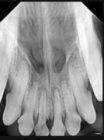

SOPIX är en DR sensor med kabel som kopplas i USB kontakten på er dator. Sensorn finns i storlekarna Size 1 (25x39mm) och Size 2 (31x42mm).

Size 1 är lämplig för katt och Size 2 för hund.

Sensorerna har en väldigt hög synbar upplösning tack vare en speciell fiberteknik, supersmå pixlar och känslig scintillator (lagret som omvandlar röntgen till elektronisk läsbart ljus). Pixlarna är endast 20um stora vilket ger en teoretisk upplösning på 25lp/mm. Kabeln är hela 370cm lång (70cm som inbyggd i Xmind Unity röntgenapparaten).